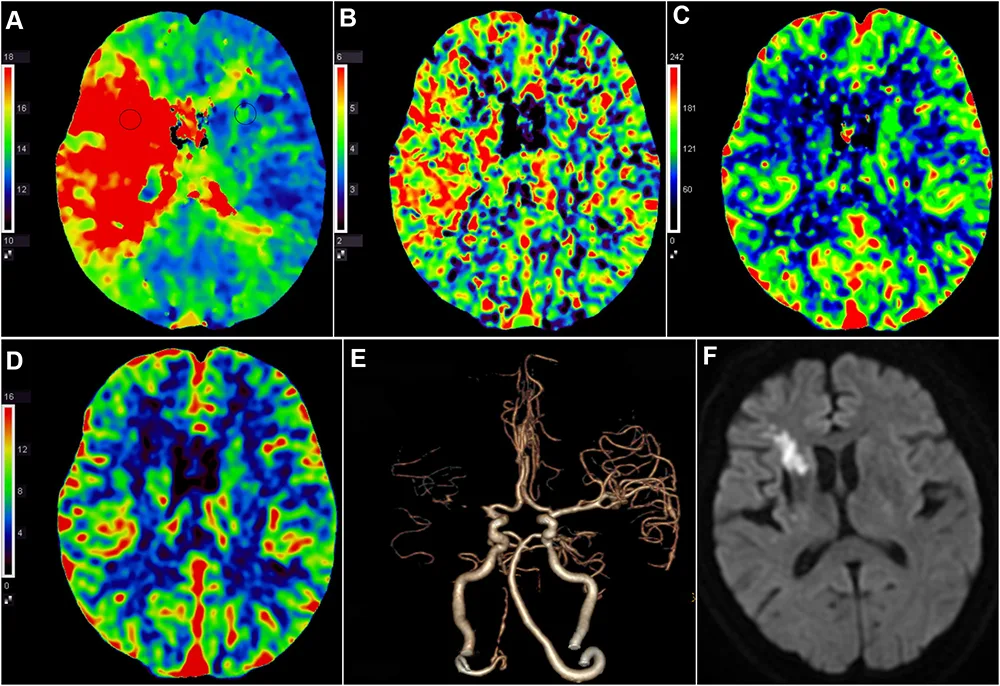

Особенно революционно ИИ проявил себя в обработке данных ПЭТ, МРТ и КТ: миллионы пикселей и сигнальных шумов, которые он разбирает как математическую картину. В этом лонгриде мы разберём, как ИИ работает, что такое PET-сканирование, и почему это — уже не будущее, а настоящее диагностики.

II. PET-сканирование: что это и почему здесь особенно нужен ИИ

Позитронно-эмиссионная томография (PET, ПЭТ) — это метод, который показывает не строение, а метаболизм тканей. В организм вводят радиоактивно меченное вещество (чаще всего глюкозу с изотопом фтора — ^18F-FDG), которое поглощается активными клетками. Камера улавливает излучение, и можно увидеть, где ткань активно «ест» энергию.

• повышать разрешение и точность распознавания мелких очагов;

• снижать дозу радиации за счёт обработки слабых сигналов;

• сравнивать динамику изменений до и после лечения.

3. Инсульт на КТ и МРТ